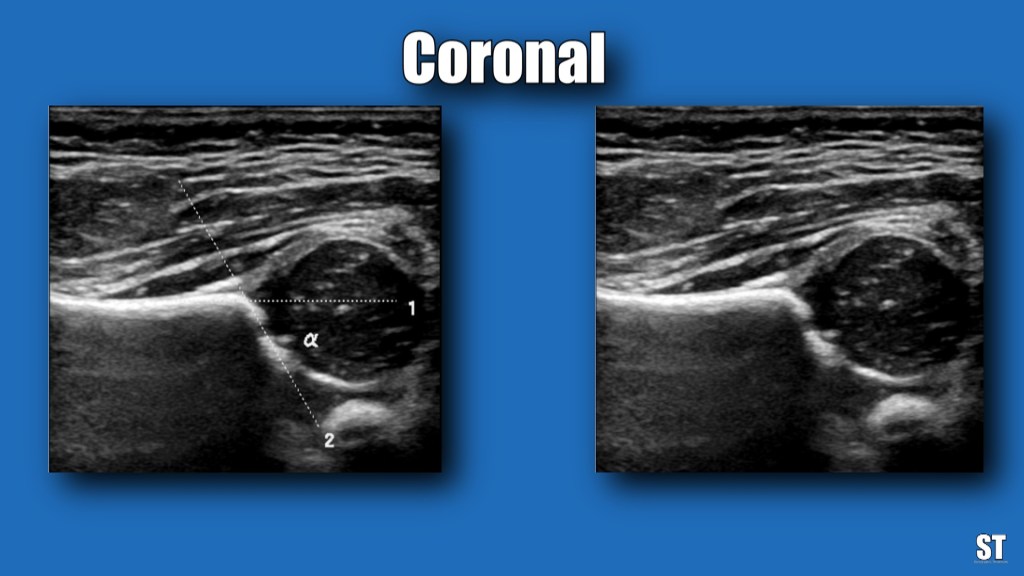

With the patient in lateral decubitus, dynamic imaging is obtained by performing Barlow (adduction or flexion) and Ortolani (abduction) maneuvers. Via the acetabulum you measure the Alpha and Beta angles.

Normal measurements are Alpha >60 degrees and Beta <55 degrees.

Measure the beta and alpha angles, asses acetabular morphology and for subluxation.